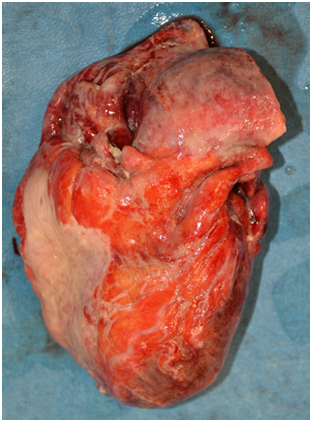

Routine dissection of all organs was done during internal examination. The brain weighed 1400g. It was dusky red in colour with marked congestion and features of meningitis. Cut sections revealed areas of necrosis with clear demarcation of grey and white matter (Figure 2). His neck structures were unremarkable. The lungs were congested and beefy red in colour, the right lung weighing 360g and the left lung 350g. No features of pulmonary embolism were evident to the naked eye. The pleural cavities contained blood-stained serous fluid, 160 ml and 200ml respectively on the left and the right sides. The pericardium contained 75ml of purulent fluid with dense adhesions to the outer surface of the heart (Figure 3). The heart weighed 360g. Major coronary arteries and their principal branches were not calcified and the maximum atherosclerotic narrowing was 30%. The heart valves appeared unremarkable.

The endocardium appeared normal and the myocardium was flabby and pale. The epicardium was covered with yellowish, shaggy fibrous exudate. The undersurface of the diaphragm overlying the surface of the liver too was covered with a thick layer of frank pus. The peritoneal cavity contained approximately 350ml of sero-purulent fluid with offensive smell. Approximately a half of the left lobe of the liver was surgically resected. Pancreaticojejunal, hepaticojejunal, gastrojejunal and jejunojejunal anastomosing sites were free of features suggestive of leakage. A thin yellow purulent exudate was seen over entire peritoneal surfaces. Remaining segments of the small intestinal serosa was congested and flakes of pus were seen adhered onto the surface. No internal hemorrhages were noticed. The large intestinal serosa was also congested and was covered with a thick layer of pus. Both kidneys were normal in size and shape but pale in colour with no visible cortico-medullary demarcation. The bladder contained small amount of cloudy urine with an offensive smell. The bladder mucosa was not shiny and was covered with a thin layer of pus. The mucosa of the ureters too had the same appearance. The remaining portion of the pancreas did not show any overt macroscopic features of acute or chronic pancreatitis. The spleen was enlarged, soft and flabby with a thin layer of pus on the outer surface. It weighed 230g (Figure 4). The histopathology confirmed the gross changes seen and some micrographs are shown here Figures 5 A‒D.